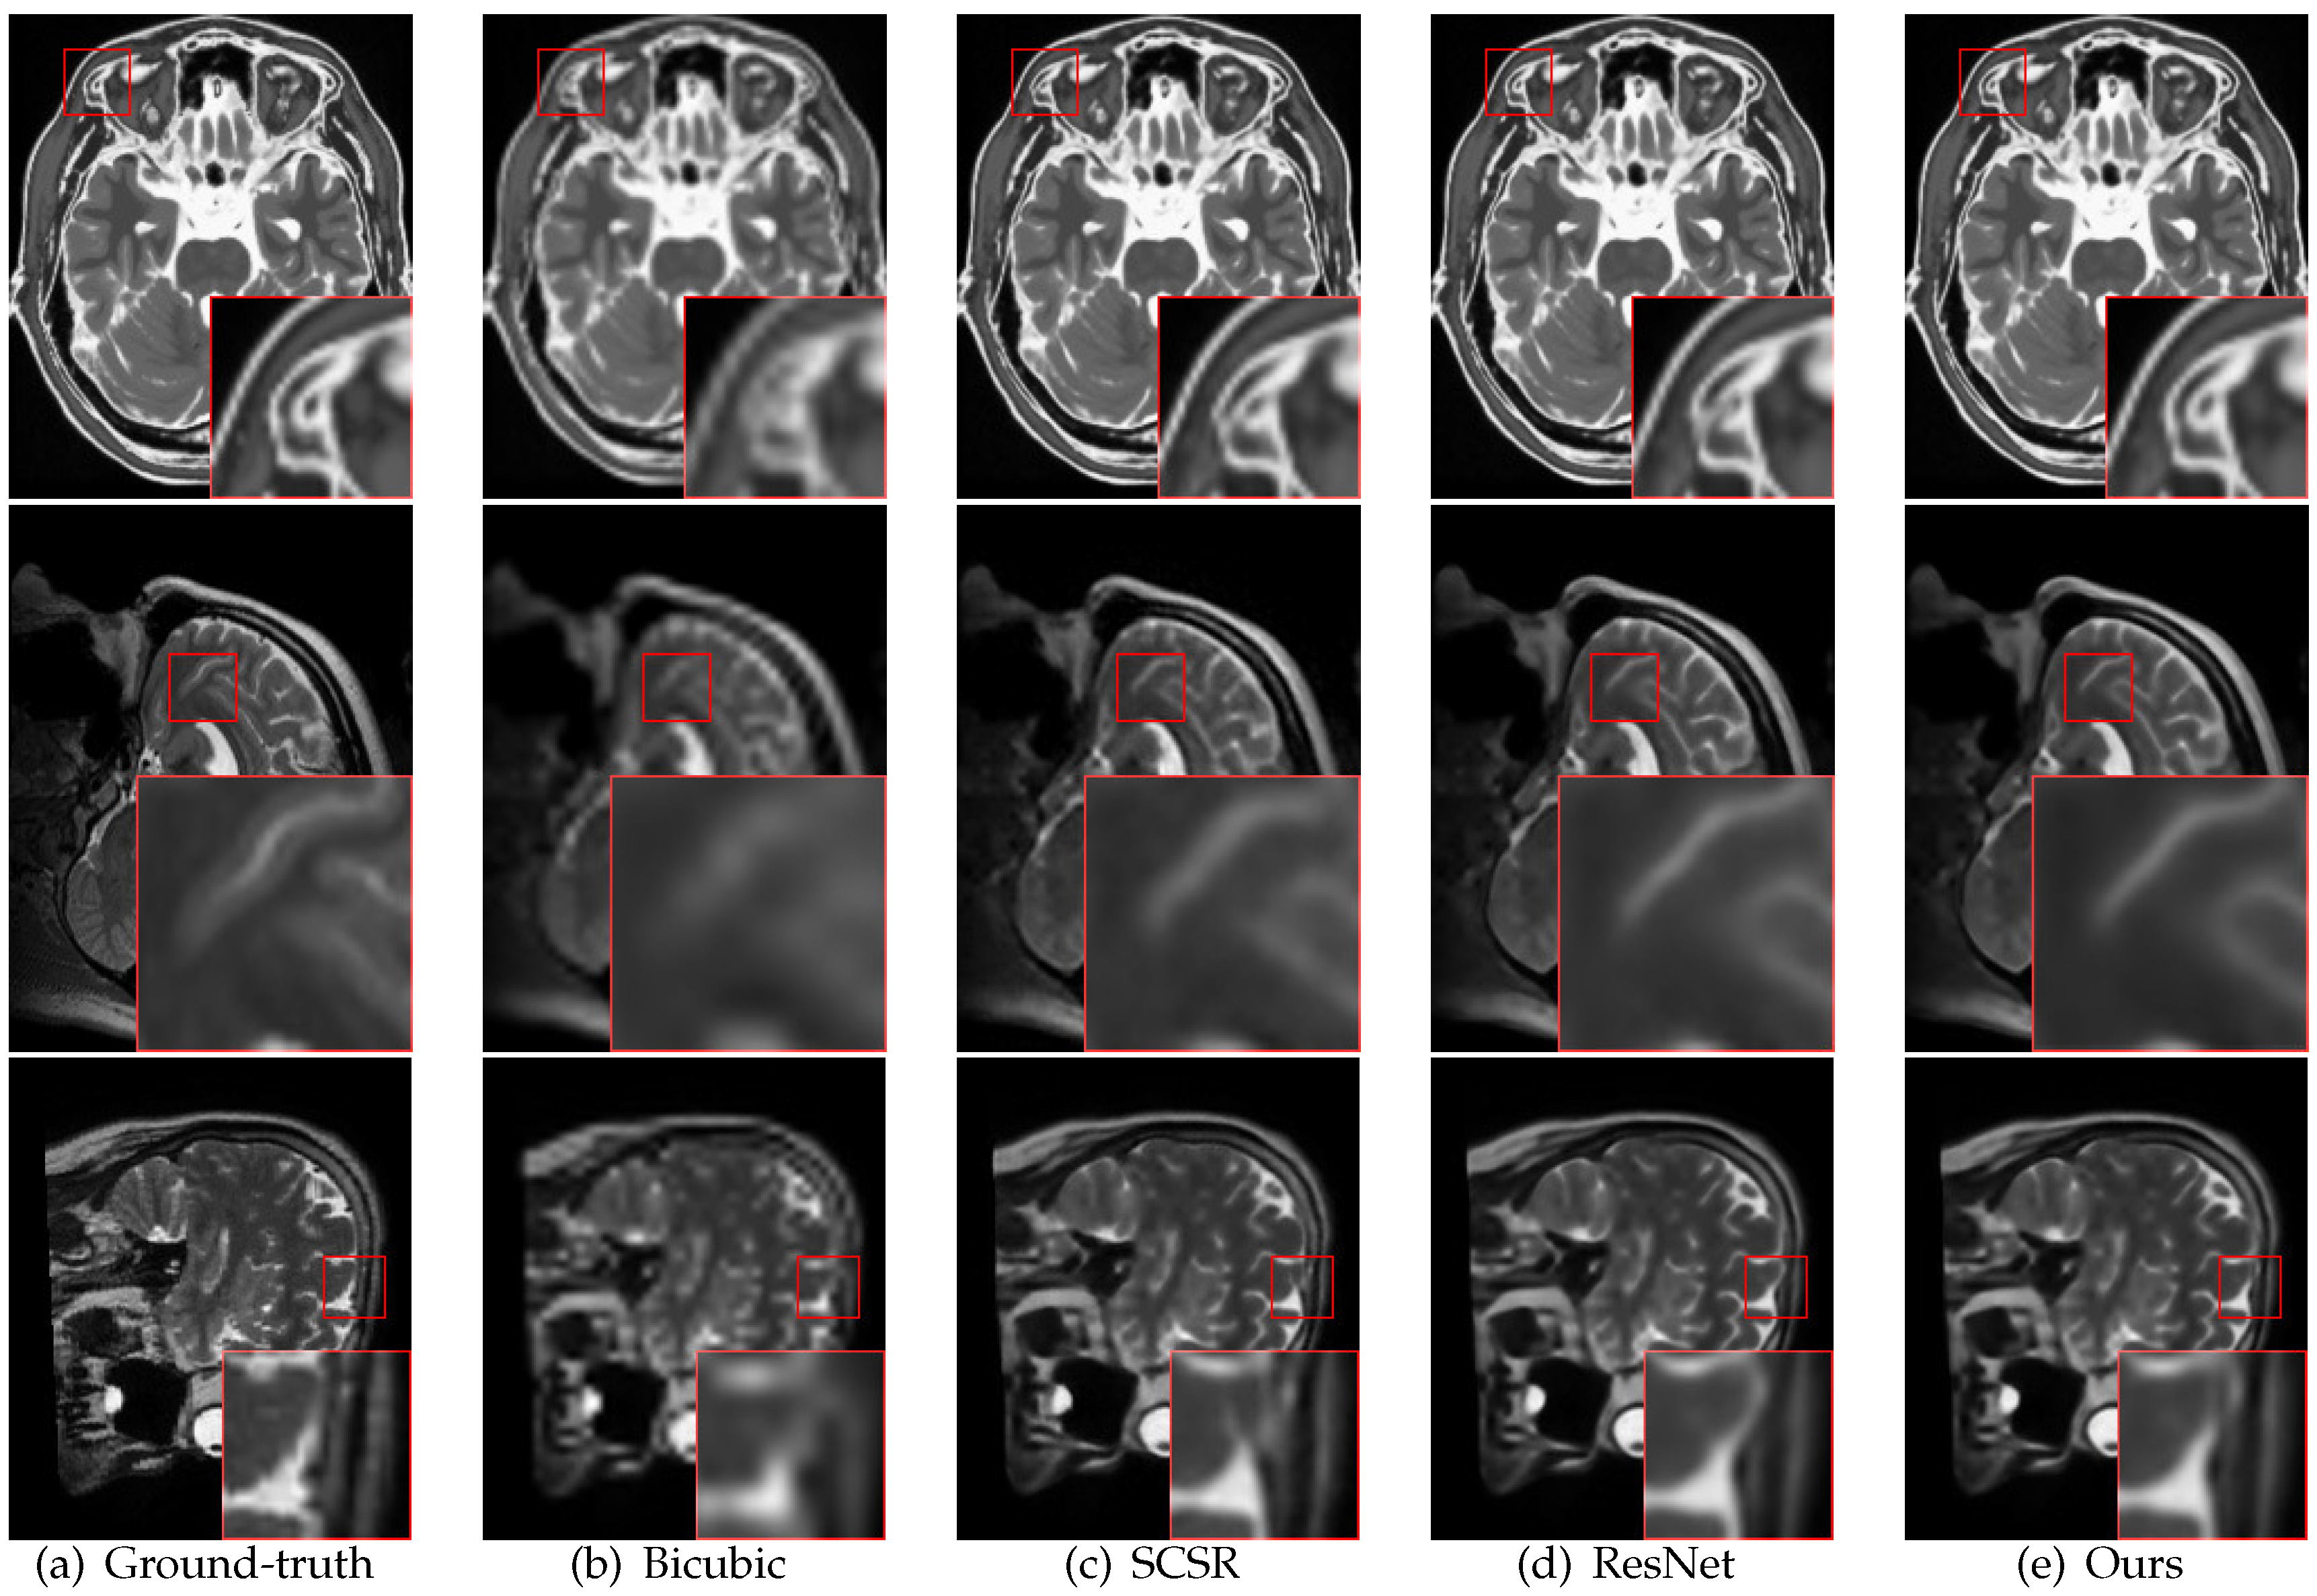

4.3. Comparison with State-of-the-Art Methods

5. Discussion